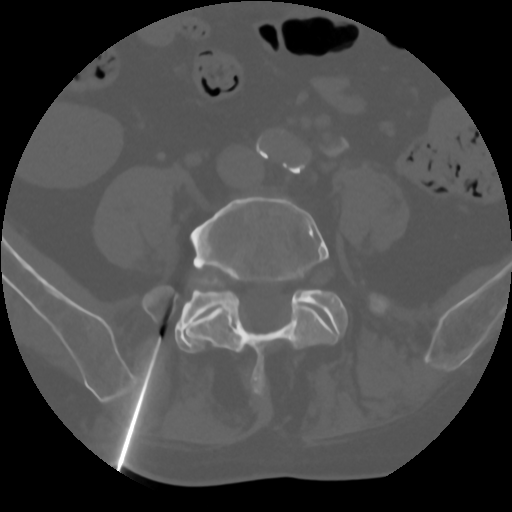

Výkon je prováděn pod CT kontrolou, což zajišťuje přesné umístění léčebné směsi složené z kortikoidu, lokálního anestetika a kontrastní látky. Podle primáře radiodiagnostického oddělení MUDr. Pavla Kedera jde o efektivní a šetrný výkon, který lze provést ambulantně.